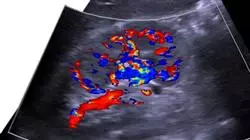

La medicina cardiorenale è un'area affascinante che affronta l'intima relazione tra cuore e reni. Comprendere le connessioni e i meccanismi alla base delle malattie cardiorenali è fondamentale per fornire ai pazienti un’assistenza sanitaria completa e di qualità. Per questo motivo, TECH Università Tecnologica ha sviluppato l'Esperto Universitario in Aggiornamento in Medicina Cardiorenale in Nefrologia, un corso post-laurea di alto livello, focalizzato sull'aiutarti ad espandere le tue conoscenze e competenze in questo campo. Durante questo corso, insegnato al 100% online, esplorerai vari argomenti fondamentali nella medicina cardiorenale. Inizierai comprendendo i concetti di base dell'anatomia e della fisiologia dei sistemi cardiovascolare e renale, ponendo le basi necessarie per affrontare le malattie che colpiscono entrambi i sistemi.